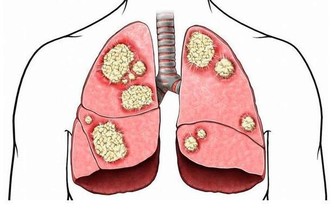

*****6.轉移灶的疼痛*****

肝癌會轉移到其他部位,比如轉移到肺部、骨骼處、那麼就可能出現骨痛、胸痛的情況。